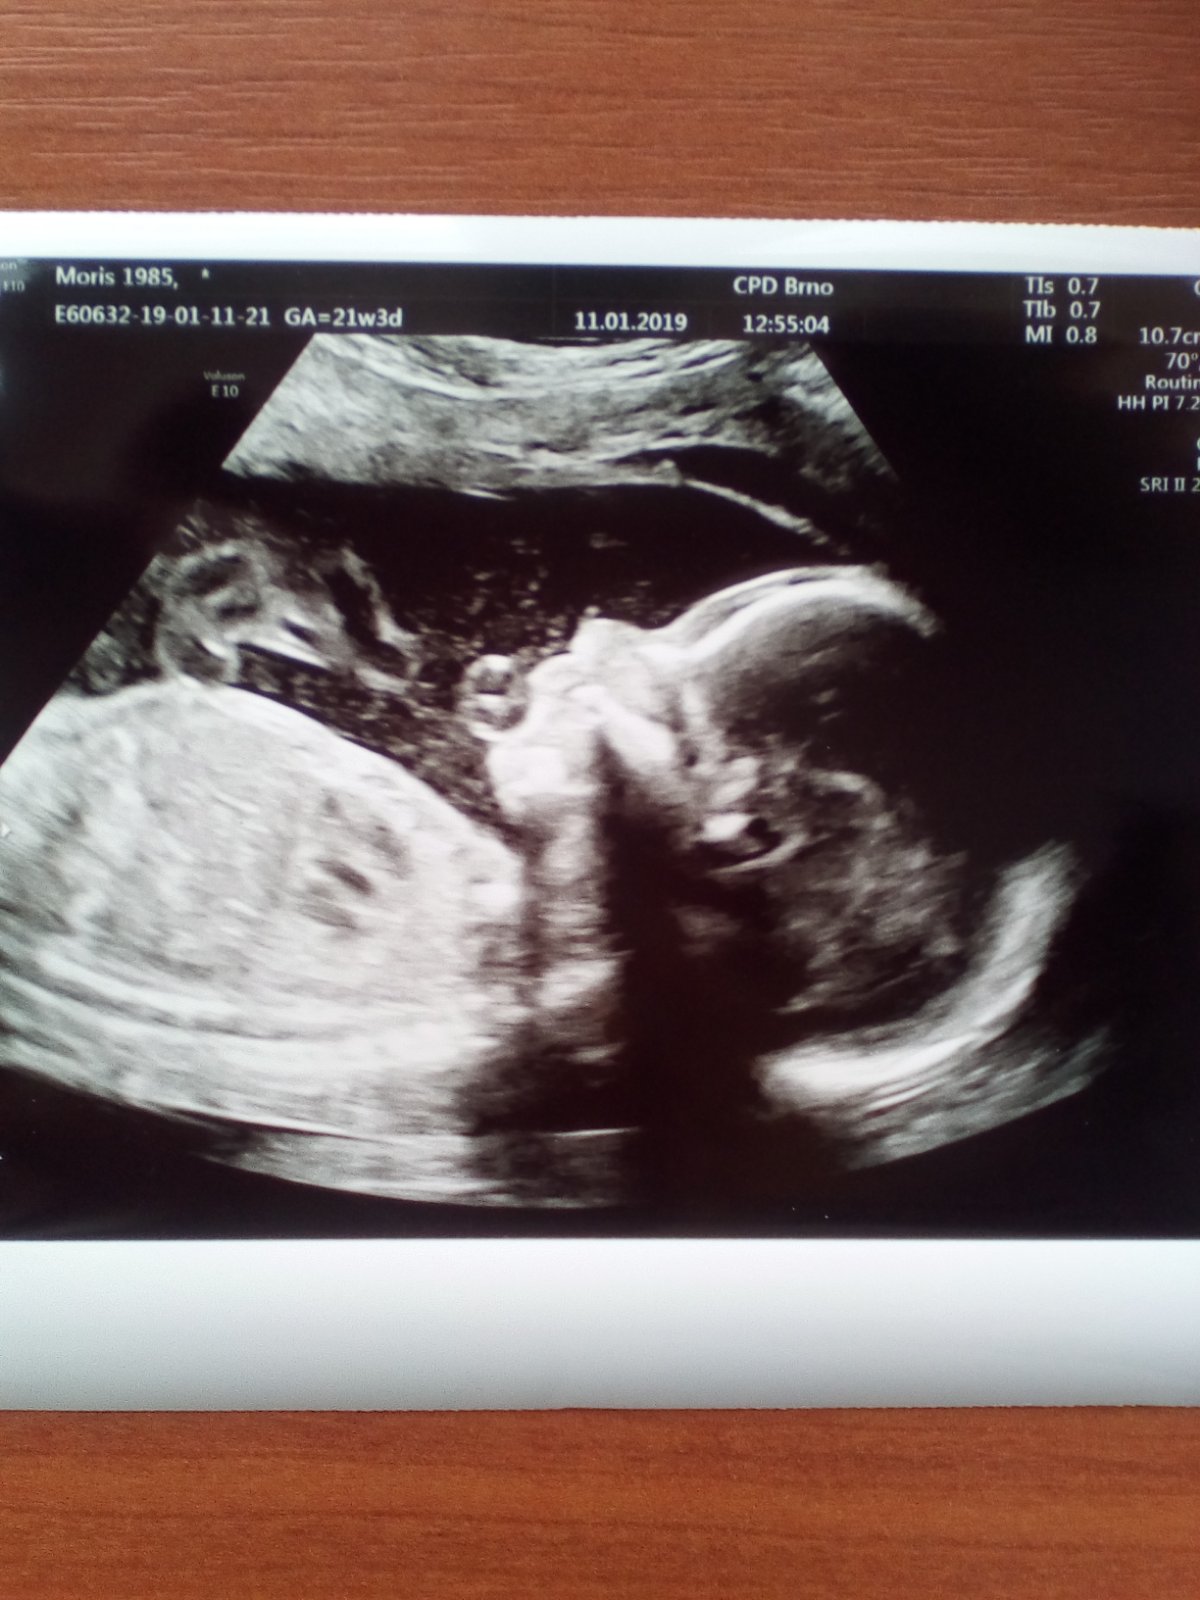

@lazuli35 děkuji 🙂 přesně pro manžela je to teď reálné, viděl jak kopal nohama dělal kotrmelce a pak mi říká : ty fakt nic necítíš? 😂 Říkám no fakt ne.. tak já mám 23.1. 2. Screening, takže obavy se zase vrací zpět, jestli vše dobře dopadne.

@horvathova3 na to se přesně těším, už minulý týden se mimčo pěkně mrskalo, tak jsem zvědavá, jaké kousky bude předvádět teď a manžel asi ani netuší, co se tam může dít 😂 ty jo, už 2. screening 😊 držím moc pěsti, ať vše vyjde!

@horvathova3 jé, tak vidíš, u tebe intuice nezafungovala 😁 my jsme byli včera na screeningu v 13+0 a vše naprosto v pořádku, riziko vyšlo vysoké 1:11 738 a vše v normě 😊 manželovi se vyšetření moc líbilo a hned se ptal, jestli bylo vidět pohlaví. A dr to zkoušela, ale že ne, že se neukázalo 😀 stejně budeme chtít obálku, manžel to chce vědět a já ne. Ale nevím, jestli to vydržím 😂